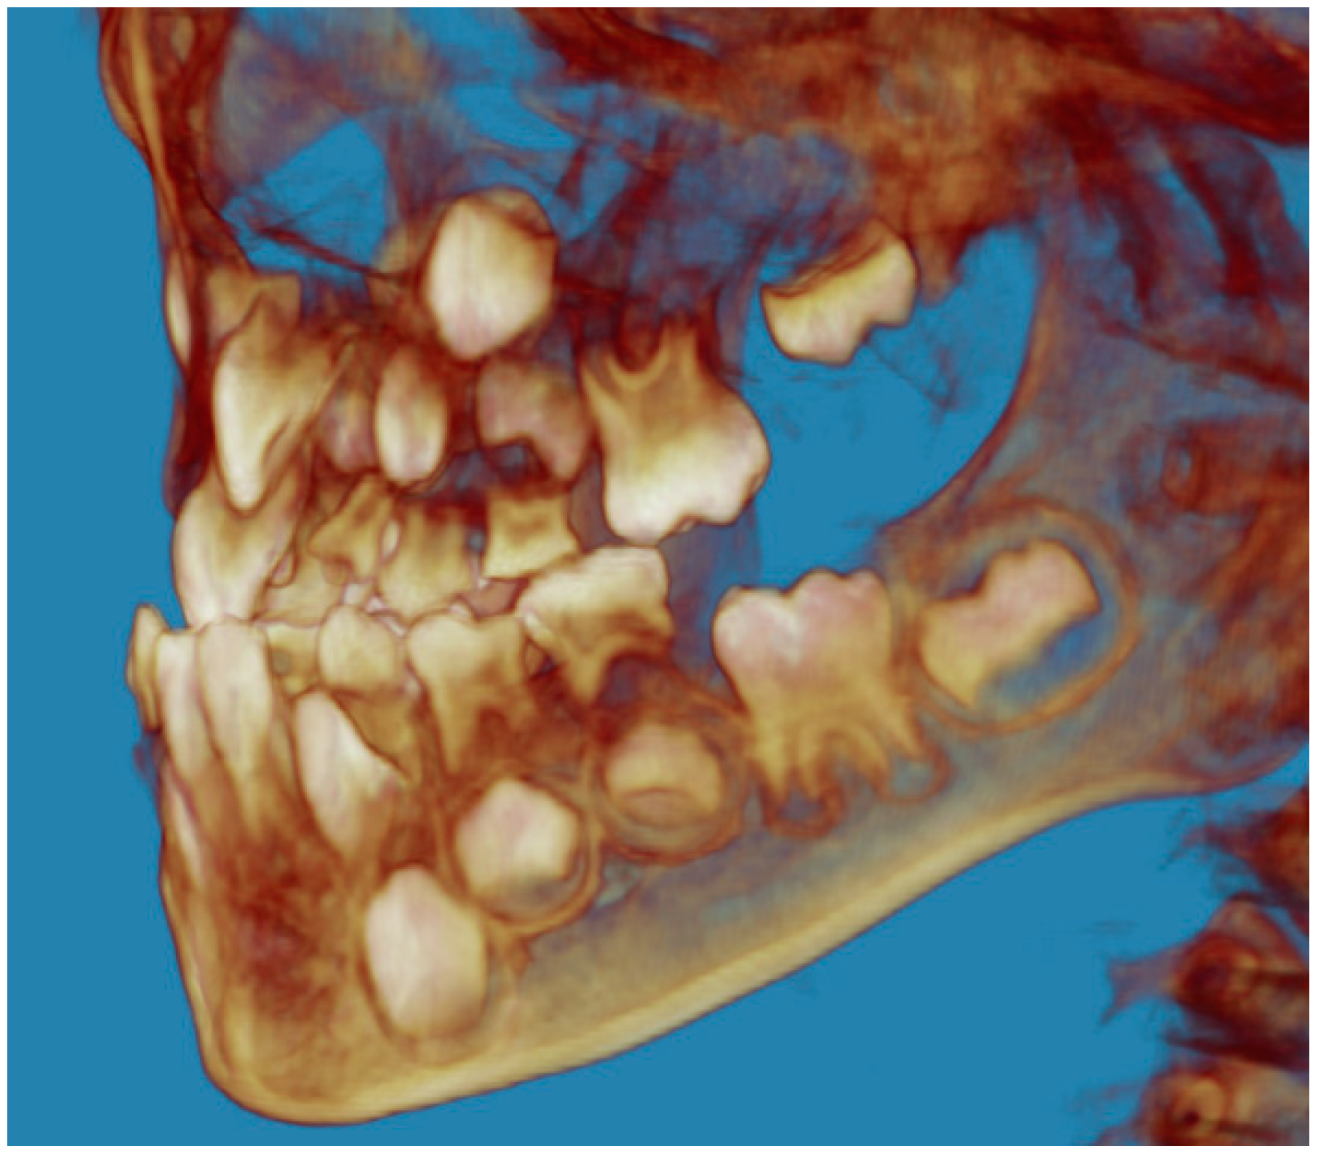

- Evaluation of impacted teeth, a common indication of CBCT in orthodontics. The advantages of CBCT include assessment of the tooth location and position, the stage of development, and status of adjacent teeth. CBCT is justified in these cases, because CBCT has the capability of evaluating the impacted teeth and adjacent structures more accurately than 2D conventional imaging. The benefit–risk ratio is favorable, especially if the CBCT volume is collimated to the impacted tooth. Figure 1, Figure 2, Figure 3 and Figure 4 show an example of impacted maxillary canines, and their proximity to the maxillary lateral incisors. Figure 1 shows an intraoral photograph. The benefit of CBCT acquisition in this case includes the ability to visualize the canines and the lateral incisors in three dimensions, which can be visualized in Figure 2 and Figure 3. In this case, the maxillary right lateral incisor exhibited external root resorption, a finding that would be difficult to see on a conventional 2D panoramic radiograph. Figure 4 shows a Maximum Intensity Projection of a panoramic view derived from the CBCT volume. This unique view is free of magnification, distortion, ghost images, and overlaps frequently seen in conventional 2D panoramic radiography.